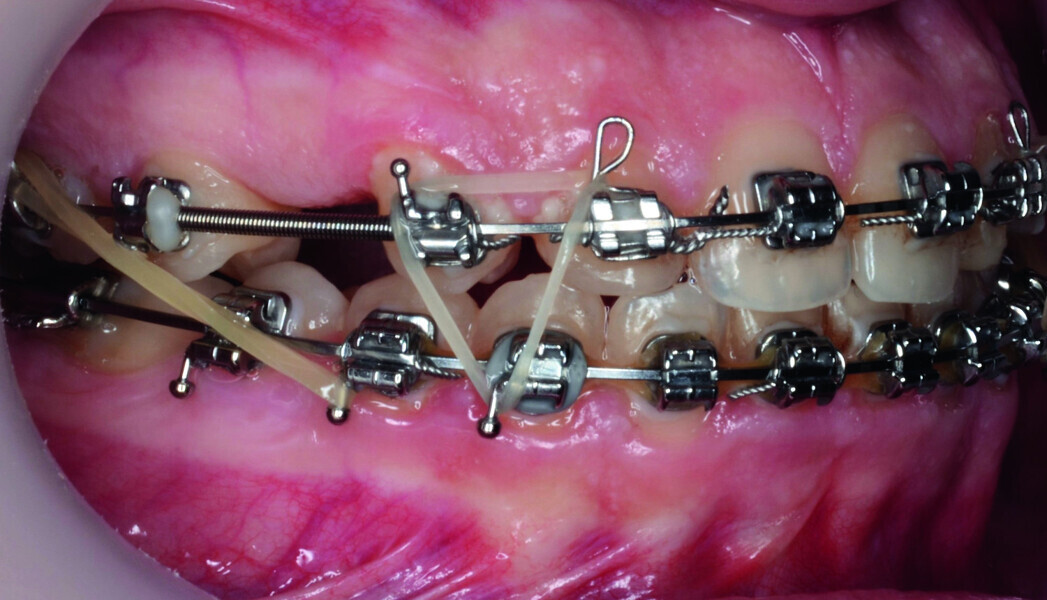

Orthodontic management of maxillary lateral incisors agenesis